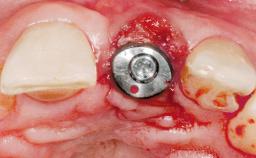

Immediate Placement of an Implant in a Maxillary Right Central Incisor Site

A 30-year-old female patient was referred to the office for the treatment of tooth 11. Her chief concern at the initial visit was to inquire, “Why is my tooth pink?” Upon clinical examination, it was determined that tooth 11 had a previous history of trauma and that the clinical crown had become noticeably pink in color as a result of internal resorption. This diagnosis was confirmed radiographically, indicating a large radiolucency involving the central and distal portions of the clinical crown. It was determined that restoration of this tooth was not possible, and that extraction was indicated. The presence of a mid-line diastema, which the patient wanted to reproduce, directed the treatment plan for tooth replacement utilizing a dental implant.

Type of Implants One-Piece|Reduced-Diameter

Bone Augmentation Horizontal|Simultaneous

Augmentation Materials Autogenous chips|Membrane

Placement Protocol Immediate implant placement

Socket Integrity Sufficient, with intact bone walls

Bone Volume Sufficient, with intact walls